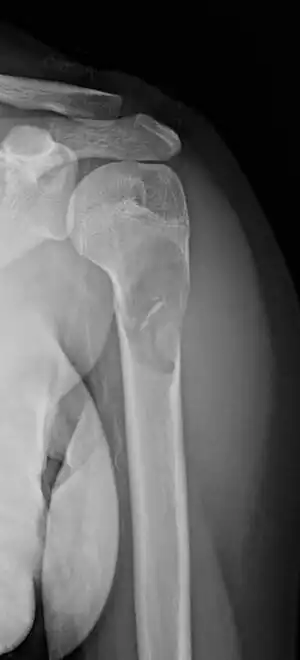

Unprovoked break in the long bone of the upper arm,, with "fallen leaf" sign.